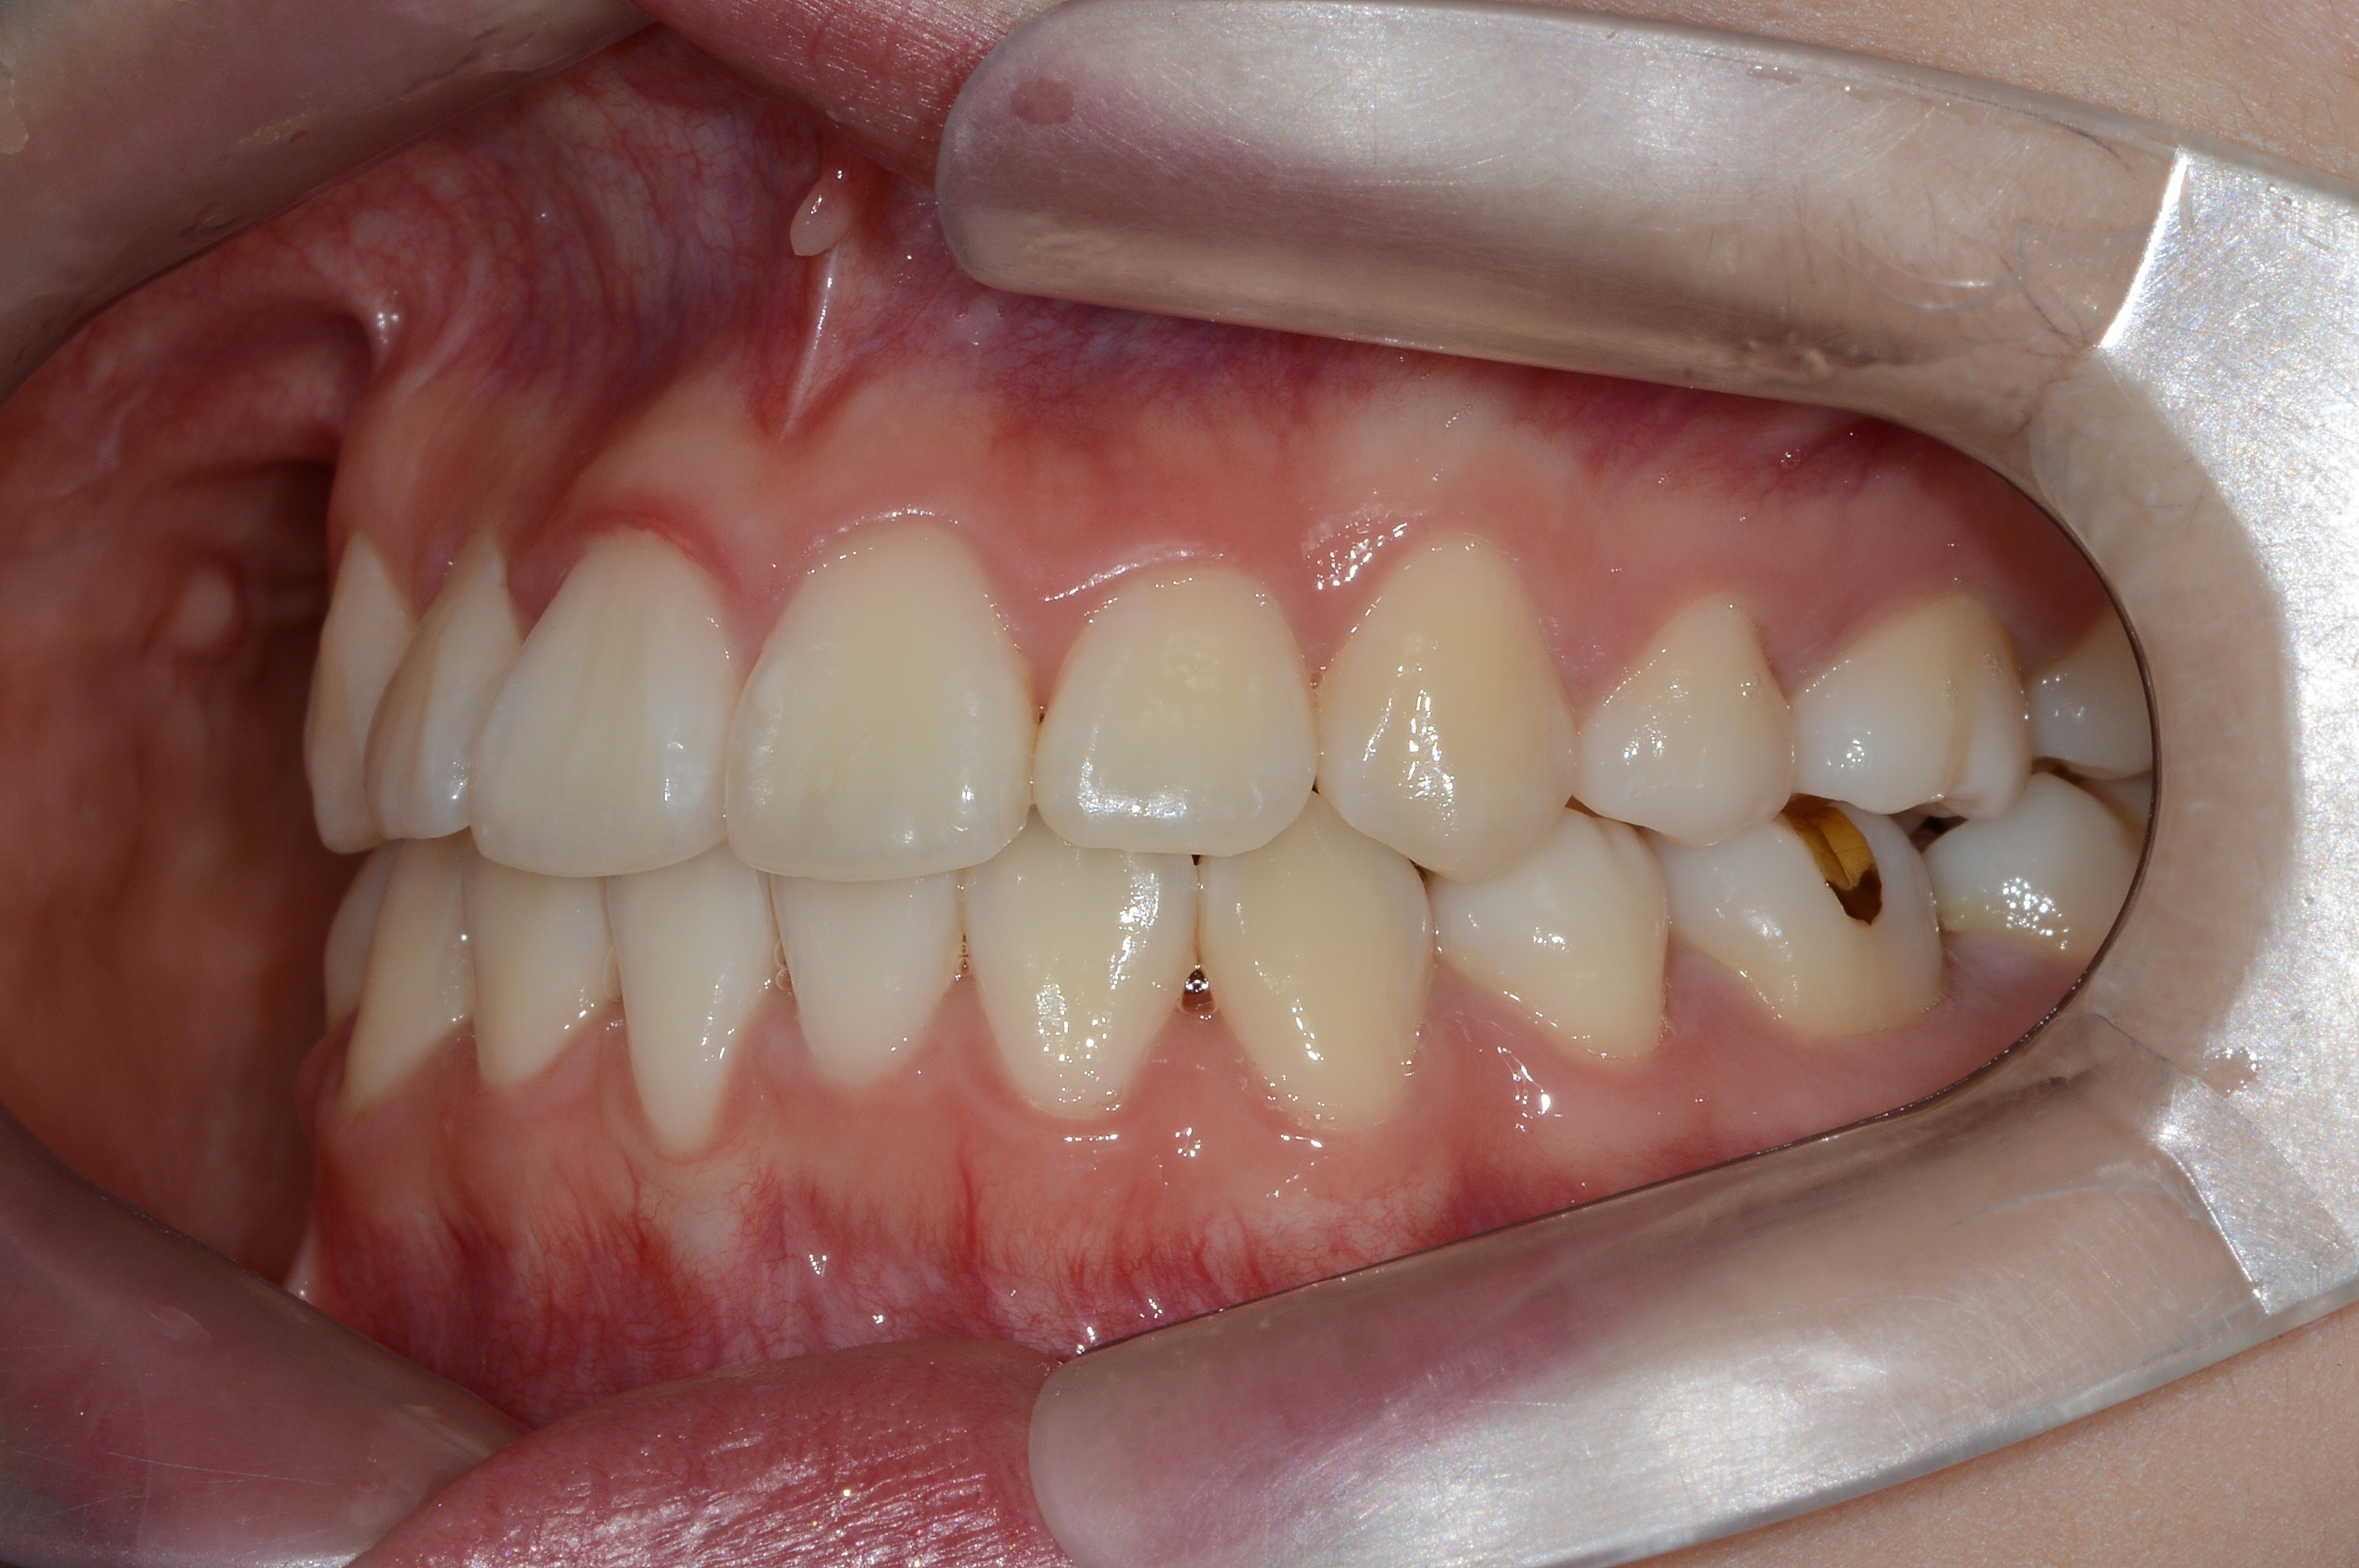

치료 전 사진입니다.